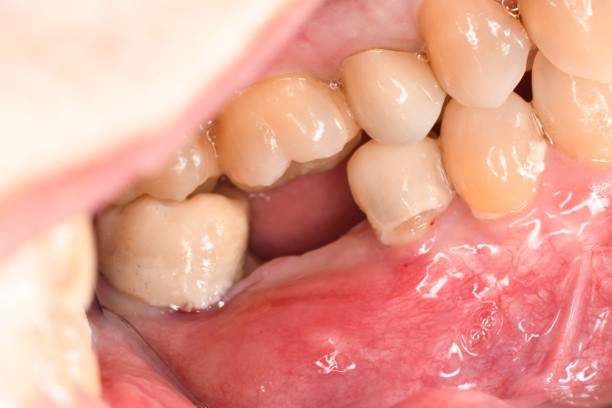

口腔内写真-1

- Befor

- After

口腔内写真-2

- Before

口腔内写真-3

| 年齢 | 40代・女性 |

|---|---|

| 主訴 | 右下7番 |

| 治療内容 | インプラント埋入 |

| 治療費 | インプラント埋入料 440,000円 GBR(骨造成) 110,000円 サージカルガイド 55,000円 2次OPE 22,000円 静脈内鎮静麻酔 77,000円 合計 704,000円 (2023年4月現在) |

| 治療期間 | 1年 |

| リスク・副作用 | インプラント手術は外科処置のため、一過性、場合によっては持続的に唇・舌・頬・口蓋・歯肉・歯牙等の感覚麻痺、切開に起因する瘢痕組織による知覚異常が起こることがあります。 インプラント手術ではドリルのようなものを使用するため接近歯の損傷が起こる事があります。 インプラント体と骨との結合不全が起こる可能性があります。 痛みや腫れは個人差もありますが、約1〜2週間程度続きます。痛みは痛み止めを服用することでしのげる程度です。 |

| 治療方針 | 右下7番は一度根管治療済みでその後痛みが出て保存不可能と判断し、抜歯を行いインプラントになりました。 骨が元々少ないので、インプラント埋入と骨造成は同時に行わず、骨造成を先に行い骨が出来るのを待ってからインプラント埋入を行う2回法で行いました。 |

| 特記事項 | インプラントは人工物なので虫歯になることはありませんが、歯周病(インプラント周囲炎)にはなります。インプラントを長持ちさせるには、毎日の歯磨きと合わせて、3〜6ヶ月ごとの定期検診でのクリーニングが大切です。 |

| 担当者所見 | かみ合わせが強くマウスピースを進めましたが、本人はマウスピースが難しいため今後ボットクスで様子を見ていきます。 |